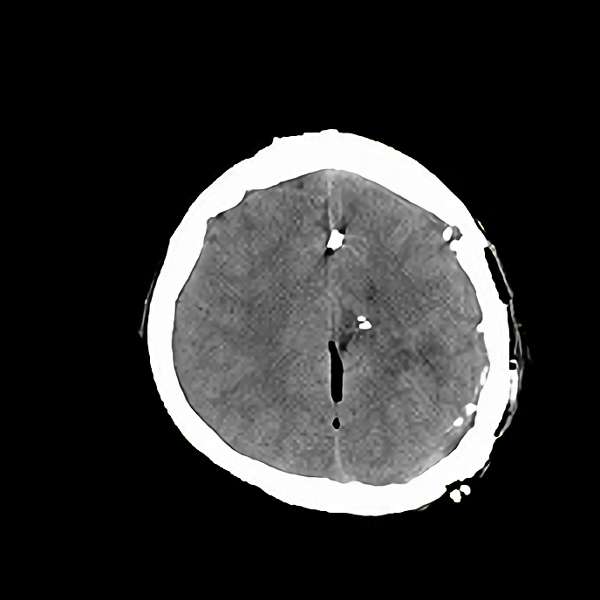

手術後